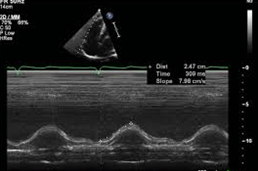

The name and description of how this measurement is performed.

What is Tricuspid Annulus Systolic Excursion - TAPSE, m-mode (zoomed preferred) through TV annulus in a right focused view in the apical 4 chamber, measure systolic waveform excursion in a vertical line?

Normal 17 mm or greater.